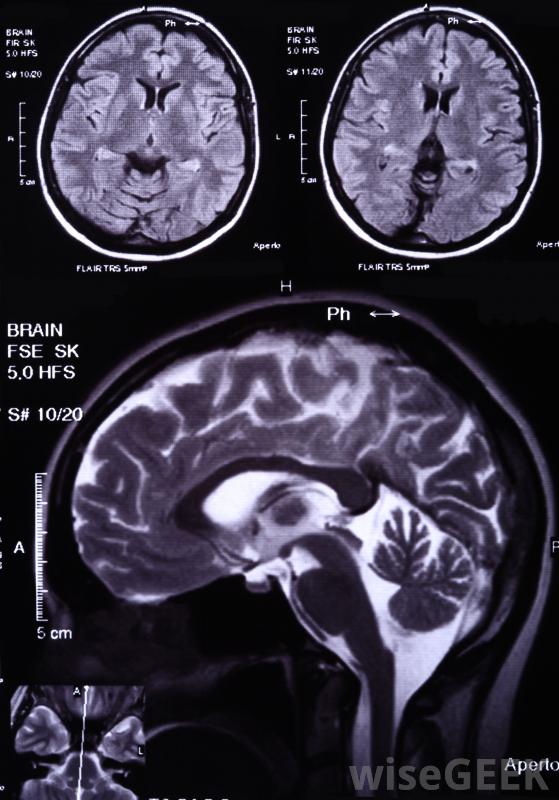

帕金森病、阿爾茨海默病和阿爾茨海默病;多發性硬化癥是與白質病變有關的一種特殊的健康狀況,它與白質病變有關。大多數情況下,首先注意到額外的癥狀,導致磁共振成像(MRI)掃描發現病變。它們通常在屏幕上顯示為白色或非常淺灰色,盡管其名稱實際上來源于浸泡在甲醛中的腦組織的顏色。這種情況的治療通常包括減緩疾病進展的藥物

腦白質病變很可能在MRI掃描中發現。